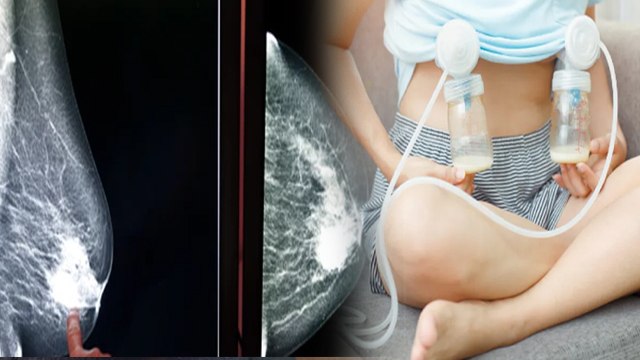

Breastfeeding - How to Use Breast Pump to Get More Breast-Milk Instead of Hand Expression 2016